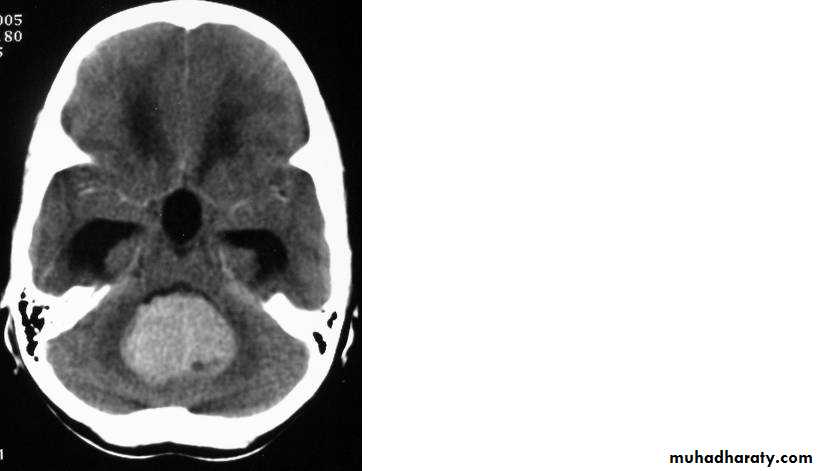

Metastatic Brain Tumours

Metastatic Brain Tumours Pre contrast CT

Metastatic Brain Tumours Post contrast CT